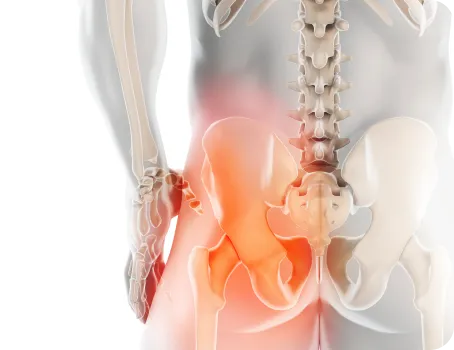

일할때 제일 많이 쓸것 같지만 실제로는 걸을때 팔을 흔드는 목적으로 제일 많이 씁니다. 골반이 틀어지면 보폭이 짧아지는 쪽이 생기게 되고, 이를 보상하기 위해 한쪽 팔을 많이 흔들게 됩니다. 결국 수십년이 지나 어깨의 회전근개가 찢어지는 문제가 생깁니다.

육체노동을 하지도 않고 외상이 없는데 젋은 나이에 회전근개 파열이 발생했다면 보행의 문제, 즉 골반의 문제로 인한 비대칭을 오래 방치한 것입니다.

따라서 어깨만 재활을 할 것이 아니라 골반교정과 척추를 같이 치료해 양쪽 어깨를 같은 범위로 흔들도록 하는 전인적 재활이 필요합니다.